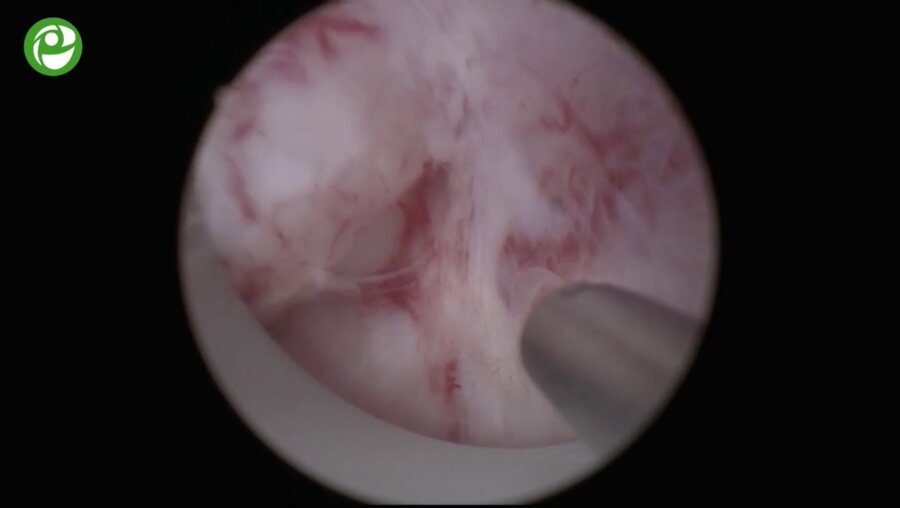

Конференция с международным участием «Высокие технологии в урологии»

Видео